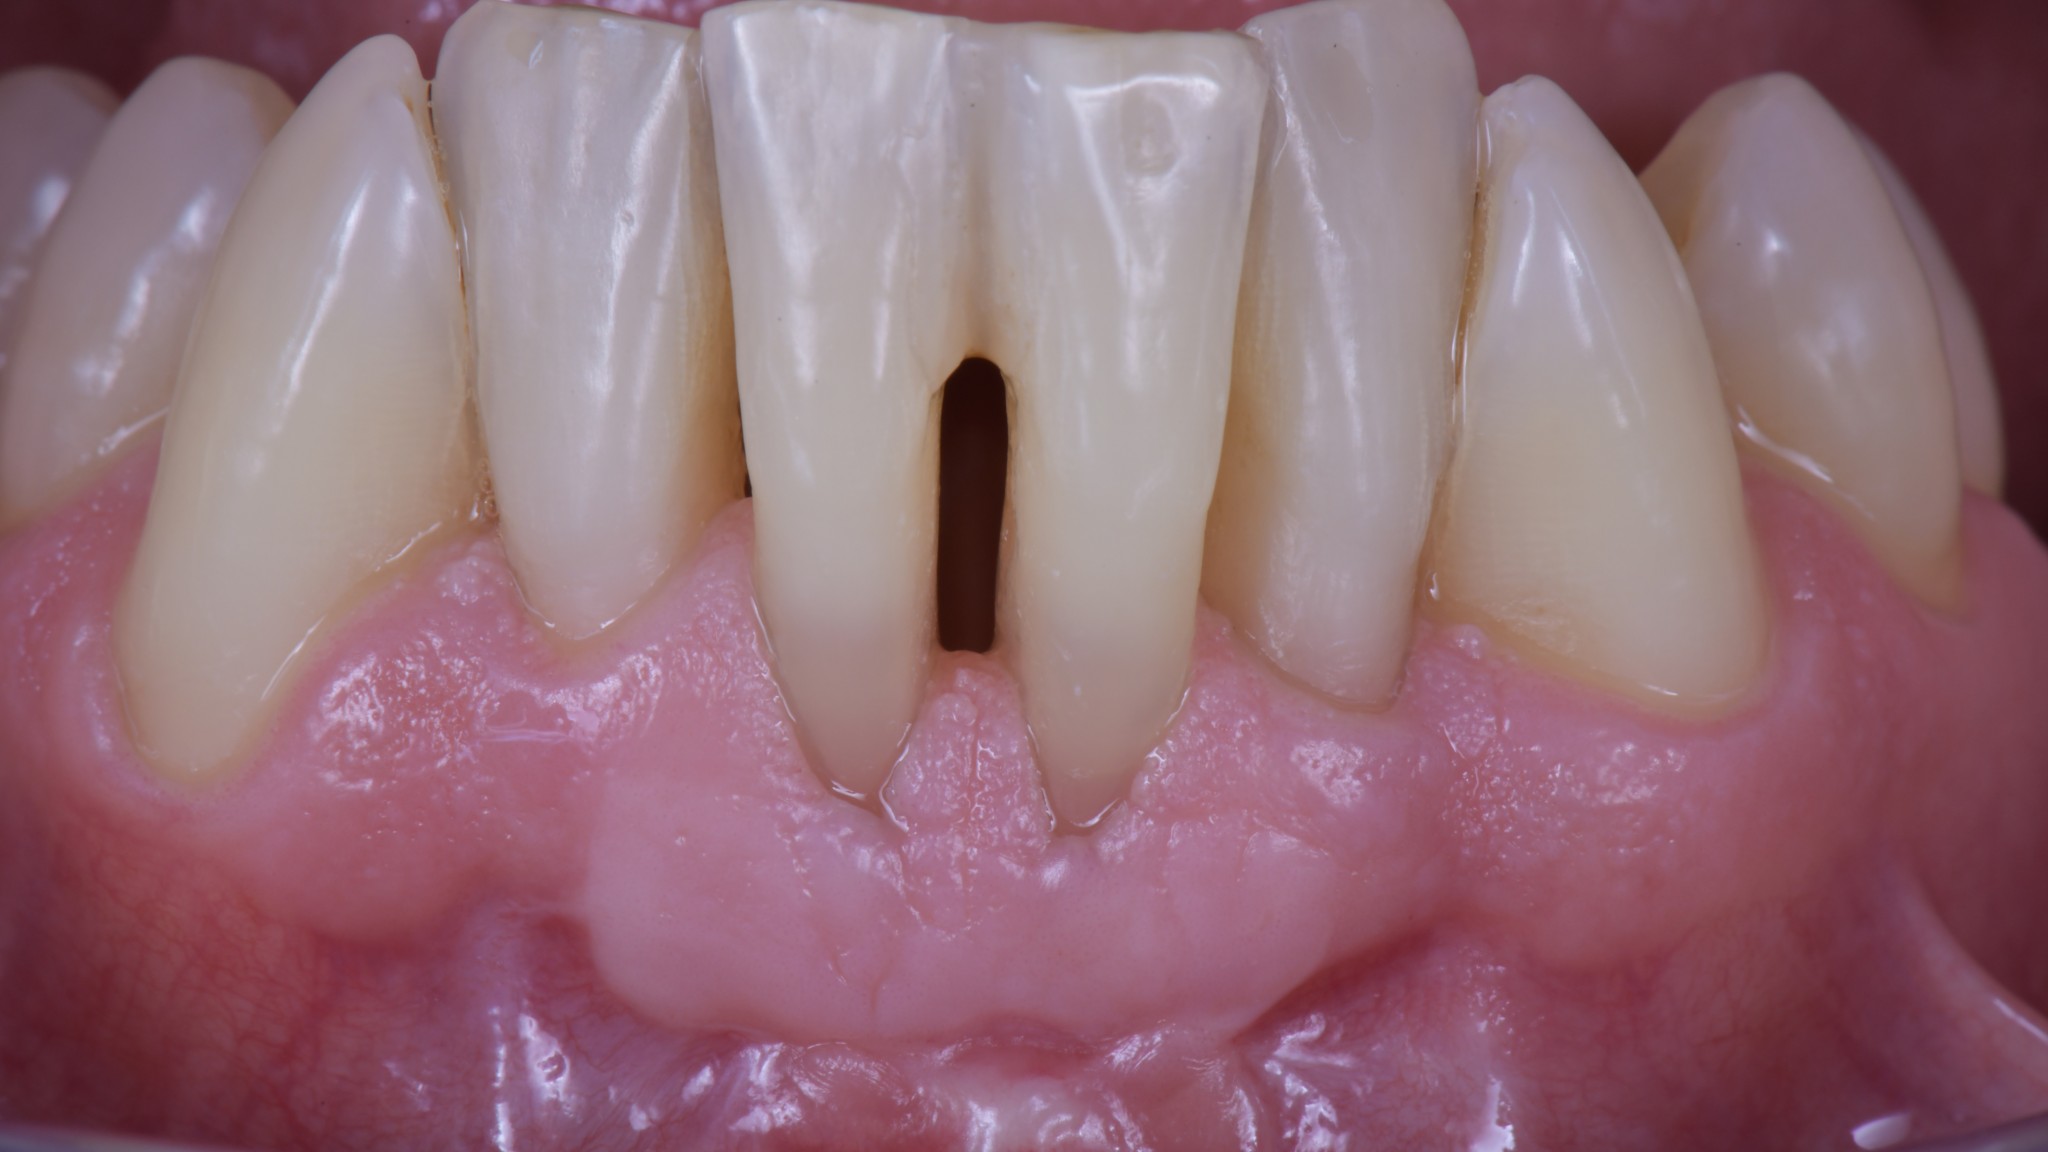

Questa è la situazione tre mesi dopo la chirurgia. L’estetica è un’altra cosa ma per questo paziente l’importante era riuscire a mantenere…